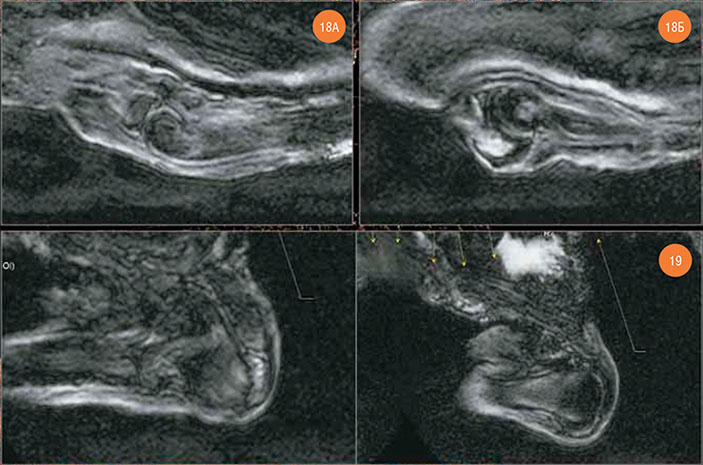

Левый локтевой сустав выглядит неизмененным, но в структуре локтевого отростка локтевой кости имеется отечный очаг размером до 9×7×8 мм.

Рис. 18. Левый локтевой сустав. А — articulatio humeroradialis, Б — articulatio humeroulnaris (в структуре olecranon’а — отечный очаг) Рис. 19. Левый плечевой сустав (параллельные срезы)

Поскольку из-за утраты мягких тканей правого плеча уровень МР-сигнала от правого плечевого сустава был низким, для его визуализации была использована технология наложения изображений программы Radiant Dicom Viever 1.9.2. По верхнему контуру головки правой плечевой кости был обнаружен дефект глубиной до 3,5–4,5 мм. Отчетливая отечная структура толщиной до 4 мм в зоне этого дефекта кости явно указывает на прижизненный травматический характер этого изменения. Отечный очаг был обнаружен и в акромеальном конце правой ключицы.